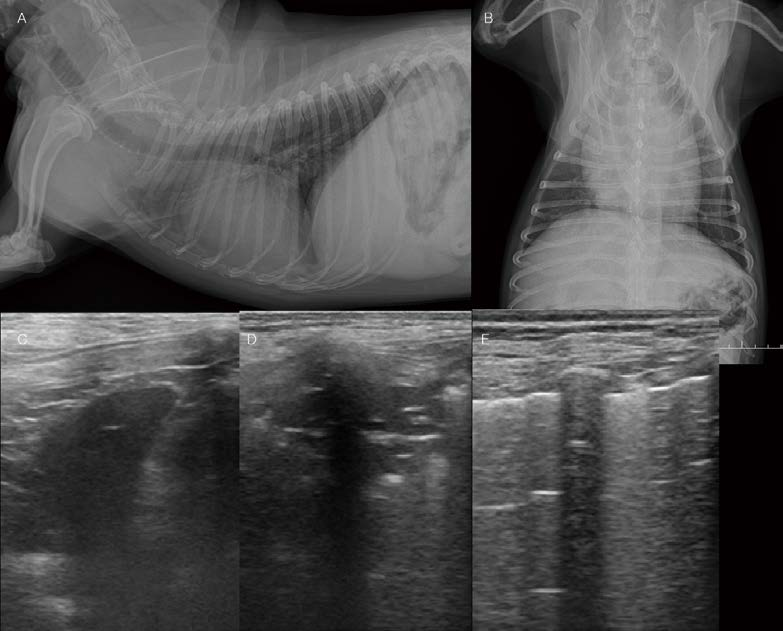

전형적이지 않는 폐렴 환자 증례입니다. 11개월 4.3kg 중성화 수컷 Maltese가 식욕저하, 기력저하, 호흡곤란 증상으로 내원하였습니다. 약 15일 전 기침 증상으로 대증 치료를 받고 일시적 개선되었던 병력이 있었습니다. 흉부방사선 검사에서 폐 전반에 걸쳐 한계가 불명확한 연조직밀도의 작은 크기의 nodular lesions이 다수 관찰됩니다(A. B). 폐초음파 검사에서 폐엽 여러 군데에서 micro-consolidation(Tiny areas of sub-pleural consolidation)이 관찰됩니다(D, E, F). 이러한 소견은 다양한 감별 진단이 가능하며, Pneumonia(e.g., fungal pneumonia, eosinophilic pneumonia…), pulmonary thromboembolism, 종양의 전이 등을 고려할 수 있습니다. 환자는 추가적인 검사가 지시되어 CT 검사, Bronchoalveolar lavage를 실시하였습니다. CT 검사에서 기관지 주변 간질에서 nodular ground glass opacity가 폐엽 전반에 걸쳐 다수 관찰됩니다. 유의적인 Pulmonary thromboembolism 소견, 다른 부위의 종양성 변화는 확인되지 않았습니다. 환자는 PCR, 배양 등의 실험실학적 검사에서 Bacillus cereus 감염원이 확인되었습니다. 항생제 감수성 검사를 바탕으로 amoxicillin/clavulanic acid, enrofloxacin 처방을 통해 환자의 임상 증상, 흉부 방사선, 페초음파는 모두 개선되었습니다. 폐초음파는 작은 병변이라도 lung periphery에 있다면 엑스레이 검사보다 훨씬 더 잘 관찰됩니다. 병변의 양상으로 감별 진단 목록을 작성하고 환자의 검사 plan을 제시할 수 있습니다. 또한 치료 과정에서 병변이 잘 개선되는지 세밀하게 확인할 수 있습니다.